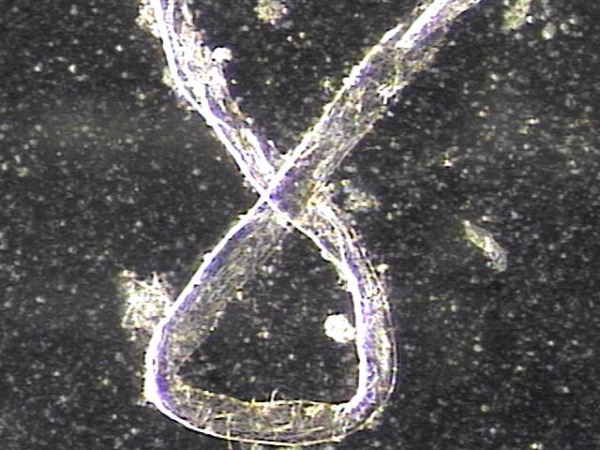

주 2회 전립선과 정낭 그리고 정관등의 표적 치료중 정관을 막고 있는 거짓중층원주상피세포와 사정되지 못한 정자들과 단백질등의 치료된 현미경학적 자료입니다.

This microscopic image was taken after repeated targeted treatment.

It shows that old cells, proteins, and sperm had collected and blocked the vas deferens.

The size of this material confirms that it was stuck inside the vas deferens.

The treatment helped to remove this blockage, allowing the ducts to open and improving the flow of semen.

사진 속 현미경 영상은 정관에서 배출된 치료 후 내용물로 보입니다. 관찰되는 소견을 근거로 말씀드리면:

길게 뻗은 섬유성 구조와 세포성 잔여물이 함께 보입니다.

이는 흔히 노화된 거짓중층원주상피세포, 단백질 덩어리, 또는 정자와 점액질이 엉겨 붙은 물질일 가능성이 높습니다.

직경이 비교적 크고 길게 뭉친 형태를 띠기 때문에, 정관 내강을 막아 정액의 흐름을 방해했을 것으로 추정됩니다.

즉, 정관을 막고 있던 주된 원인은

오래된 상피세포 찌꺼기, 단백질 응집물, 그리고 사정되지 못하고 고여 있던 정자들이 엉겨 형성된 덩어리(blockage material) 로 보입니다.

This microscopic image shows material that was removed after targeted treatment of the vas deferens.

The findings suggest that the blockage was mainly caused by:

- Old cells that had shed from the lining,

- Protein debris, and

- Sperm that could not be released and became trapped.

These substances clumped together over time and formed a plug large enough to block the vas deferens, preventing normal flow.

The treatment helped clear this material, allowing for better passage through the duct.